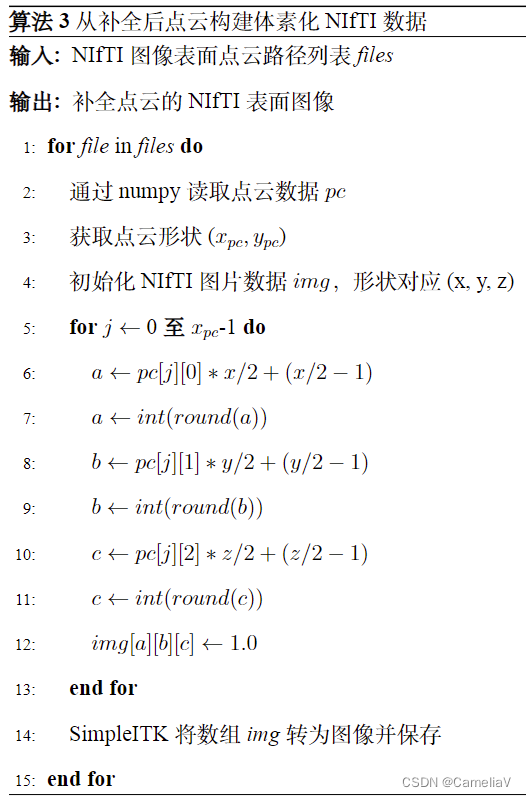

算法(伪代码)

参考示例效果:

参考示例:

\begin{algorithm}[H]

\caption{从补全后点云构建体素化NIfTI数据}

\begin{algorithmic}[1]

\REQUIRE NIfTI图像表面点云路径列表\textit{files}

\ENSURE 补全点云的NIfTI表面图像

\FOR{\textit{file} in \textit{files}}

\STATE 通过numpy读取点云数据$pc$

\STATE 获取点云形状($x_{pc}, y_{pc}$)

\STATE 初始化NIfTI图片数据$img$,形状对应(x, y, z)

\FOR{$j$ $\gets$ 0 \textbf{至} $x_{pc}$-1}

\STATE $a \gets pc[j][0] * x / 2 + (x / 2 - 1)$

\STATE $a \gets int(round(a))$

\STATE $b \gets pc[j][1] * y / 2 + (y / 2 - 1)$

\STATE $b \gets int(round(b))$

\STATE $c \gets pc[j][2] * z / 2 + (z / 2 - 1)$

\STATE $c \gets int(round(c))$

\STATE $img[a][b][c] \gets 1.0$

\ENDFOR

\STATE SimpleITK将数组\textit{img}转为图像并保存

\ENDFOR

\end{algorithmic}

\end{algorithm}